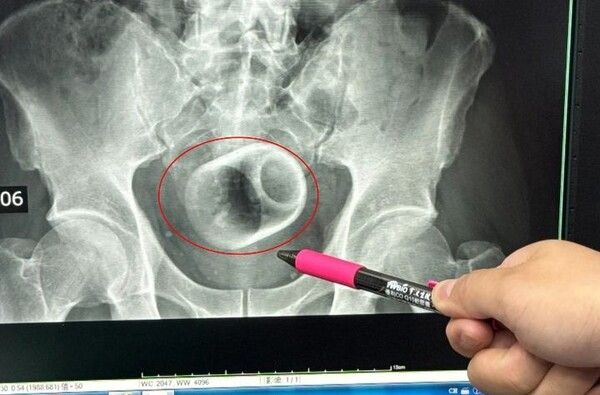

엑스레이 촬영 결과 컵은 A씨의 대장에 완전히 끼어 있었으며 장 일부는 괴사 상태였다. 그는 엄청난 복통과 복부 팽만감을 호소했고 즉시 수술실로 이송됐다.